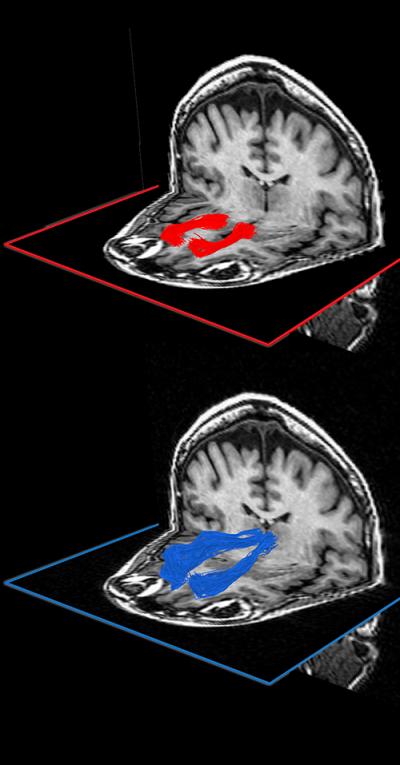

The critical white-matter connections that the experiment identified run from the thalamus, a highly connected relay center in the brain, to the medial prefrontal cortex, an area of the brain involved with decision making, and from the medial prefrontal cortex to the ventral striatum, which is associated with the emotional and motivational aspects of behavior.

On the same day, the participant's brains were scanned using a relatively new MRI technique called diffusion tensor imaging (DTI). In the last 20 years, most brain imaging research has been done with fMRI, an imaging method that measures variations in the oxygen consumption in different areas of the grey matter, which correspond to variations in neuron activity levels. By contrast, DTI detects the water trapped by the myelin sheaths that surround the axons in white-matter regions and produces a signal related to the density, diameter and amount of myelination of the axons (a combination the researchers call 'integrity').